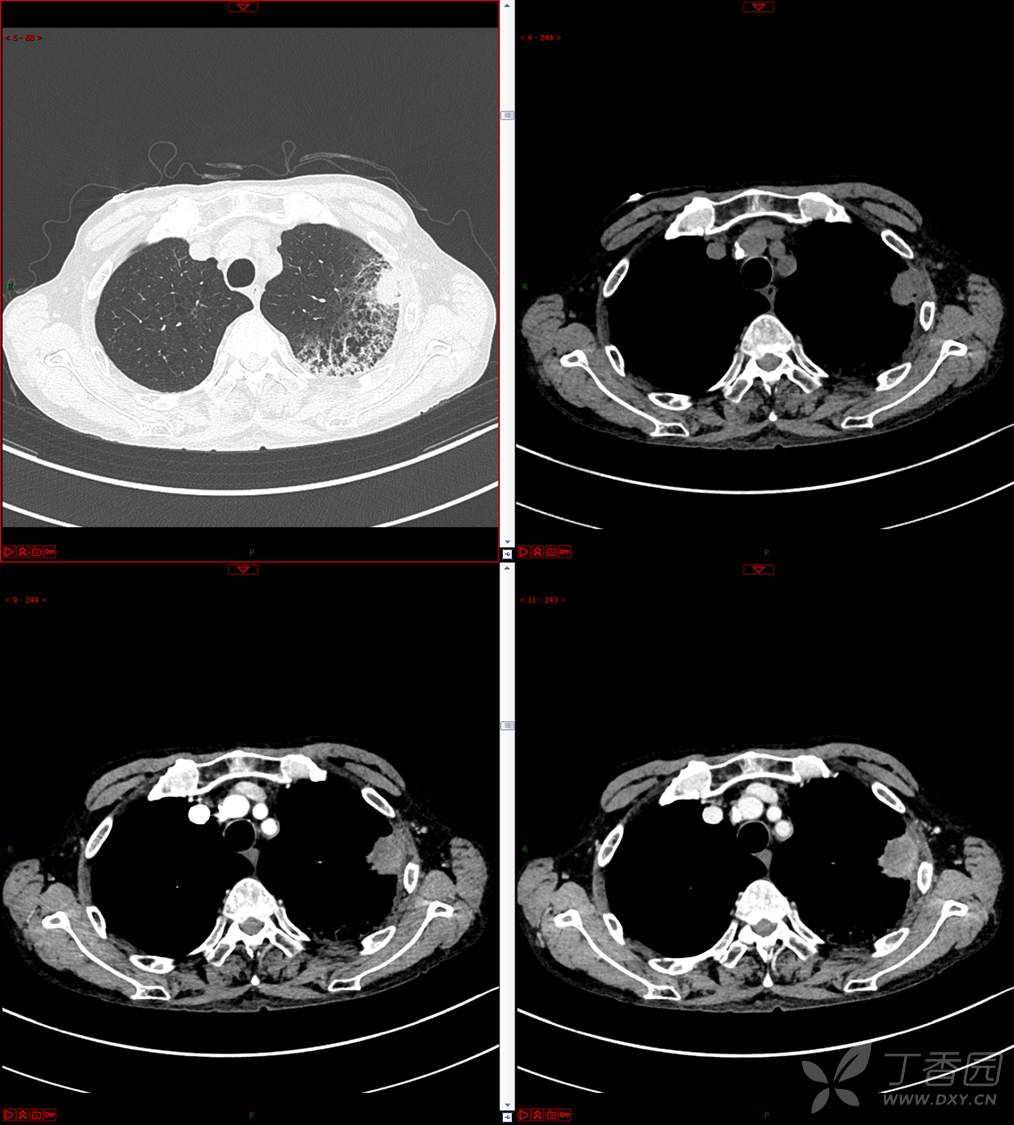

现病史:患者自诉5月前无明显原因及诱因出现纳差、乏力,伴进食后腹胀,无腹痛、腹泻、发热、盗汗、恶心、胸闷,未行特殊处理。1月前无明显原因诱因出现咳嗽,呈阵发性,咳白痰,痰中带鲜红色血丝,10余口/日,无血块,仍伴纳差、乏力、进食后腹胀,无恶心、呕吐、呕血,无头晕、心慌、喘憋、胸闷。在家未行特殊治疗,来我院就诊,2022.8.18行胸部(肺)CT平扫:左上肺占位并左侧肋骨骨质破坏,考虑间叶源性恶性肿瘤。门诊以“肺肿物”收入我科。患者自发病以来,神志清,精神可,饮食差,睡眠可,二便正常,近3月减轻5Kg。